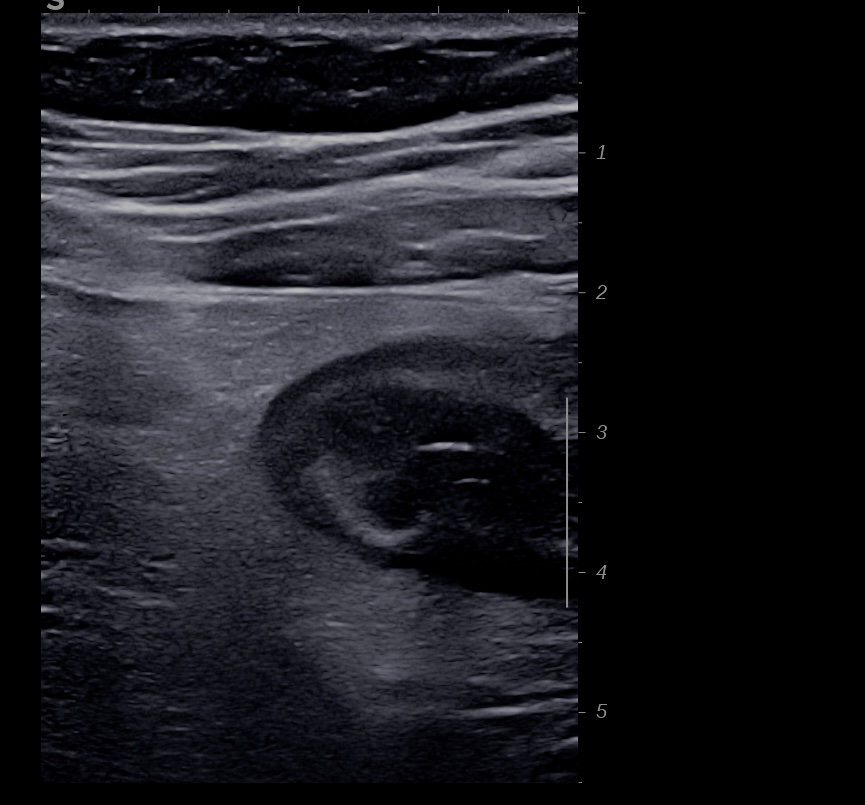

Patiente revue 4 ans plus tard sous vedolizumab Entiyo® en rémission clinique complète, biologie et calprotectine fécale normales, l’échographie (mauvaise échogénicité de la patiente) montre une paroi normalisée entre 1,8 et 2,8 mm d’épaisseur structure en couche conservée.

Le score de Milan MUC est à 3.92 confirmant la rémission échographique